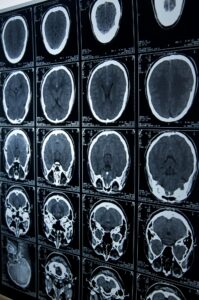

As a Cleveland, Ohio brain injury lawyer representing victims of brain injury, we face many other challenges. Family members coping with behavioral and cognitive changes caused by organic brain damage require emotional support and counseling. Often, family, friends and business associates must be interviewed to establish a complete picture of the injured party’s pre-injury and post-injury condition. While some medical testing can show objective evidence of brain injury, the injury is often evasive and objectively provable only on autopsy. As we learned from studies involving military combatants and professional athletes, chronic traumatic encephalopathy (CTE) does not always show up on imaging studies such as MRI. That does not rule-out the diagnosis.

Our firm handles cases where surgical mistakes, anesthesia mismanagement, or failure to diagnose brain conditions result in lasting damage to the brain. This includes instances where critical imaging like X-rays or MRIs were misread, delaying essential treatment. We also pursue claims involving abnormal lab results that were overlooked or incorrectly interpreted, contributing to the progression of undiagnosed brain injuries. Our Cleveland brain injury lawyer is ready to represent your case, no matter how it has developed.